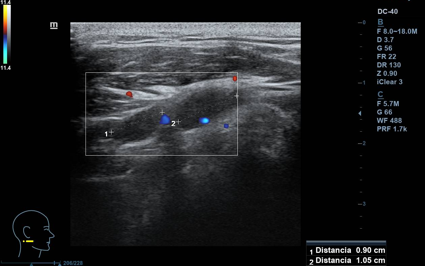

Lesión hipoecogénica cervical de aspecto sólido, de 2,5 x 1 cm (ancho x alto), con hilio vascular que preserva, impresiona de residual, vascularizado (Doppler). Otras lesiones similares de menor tamaño, pero con hilio mejor preservado, de aspecto benigno. Todas las lesiones impresionan de adenopatías. A nivel contralateral: lesiones similares en menor cuantía, también de aspecto benigno. Tiroides normal.